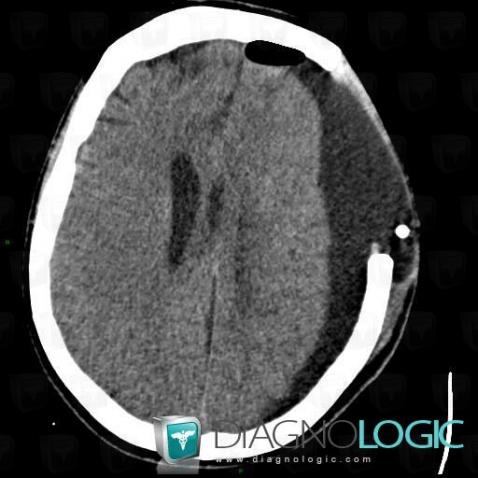

- Diagnostic Hygrome sous dural, Localisation(s) Espaces peri cérébraux supratentoriels, comportant les gammes Lésion extra axiale supra tentorielle